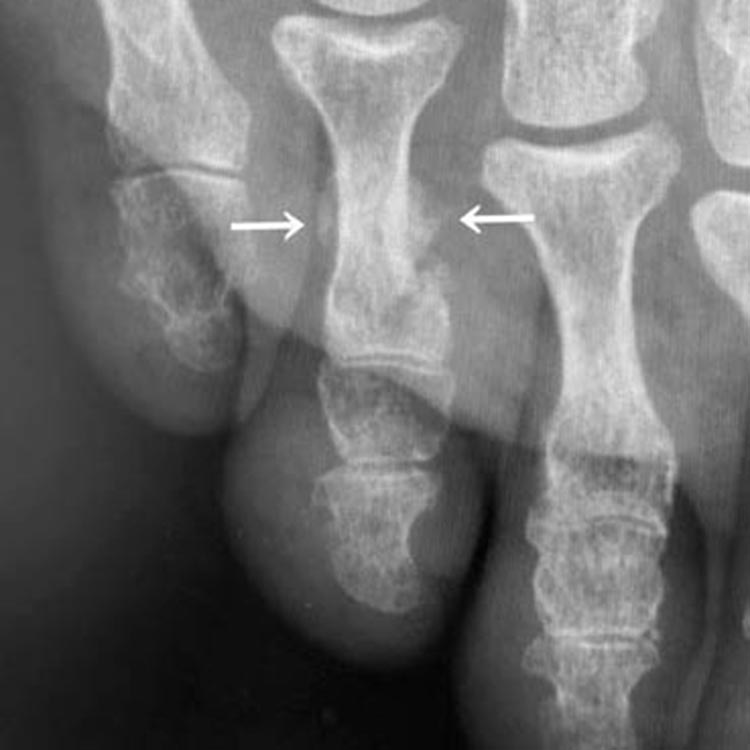

受傷直後のレントゲン写真

受傷直後(わかりにくいですが矢印が骨折部です)